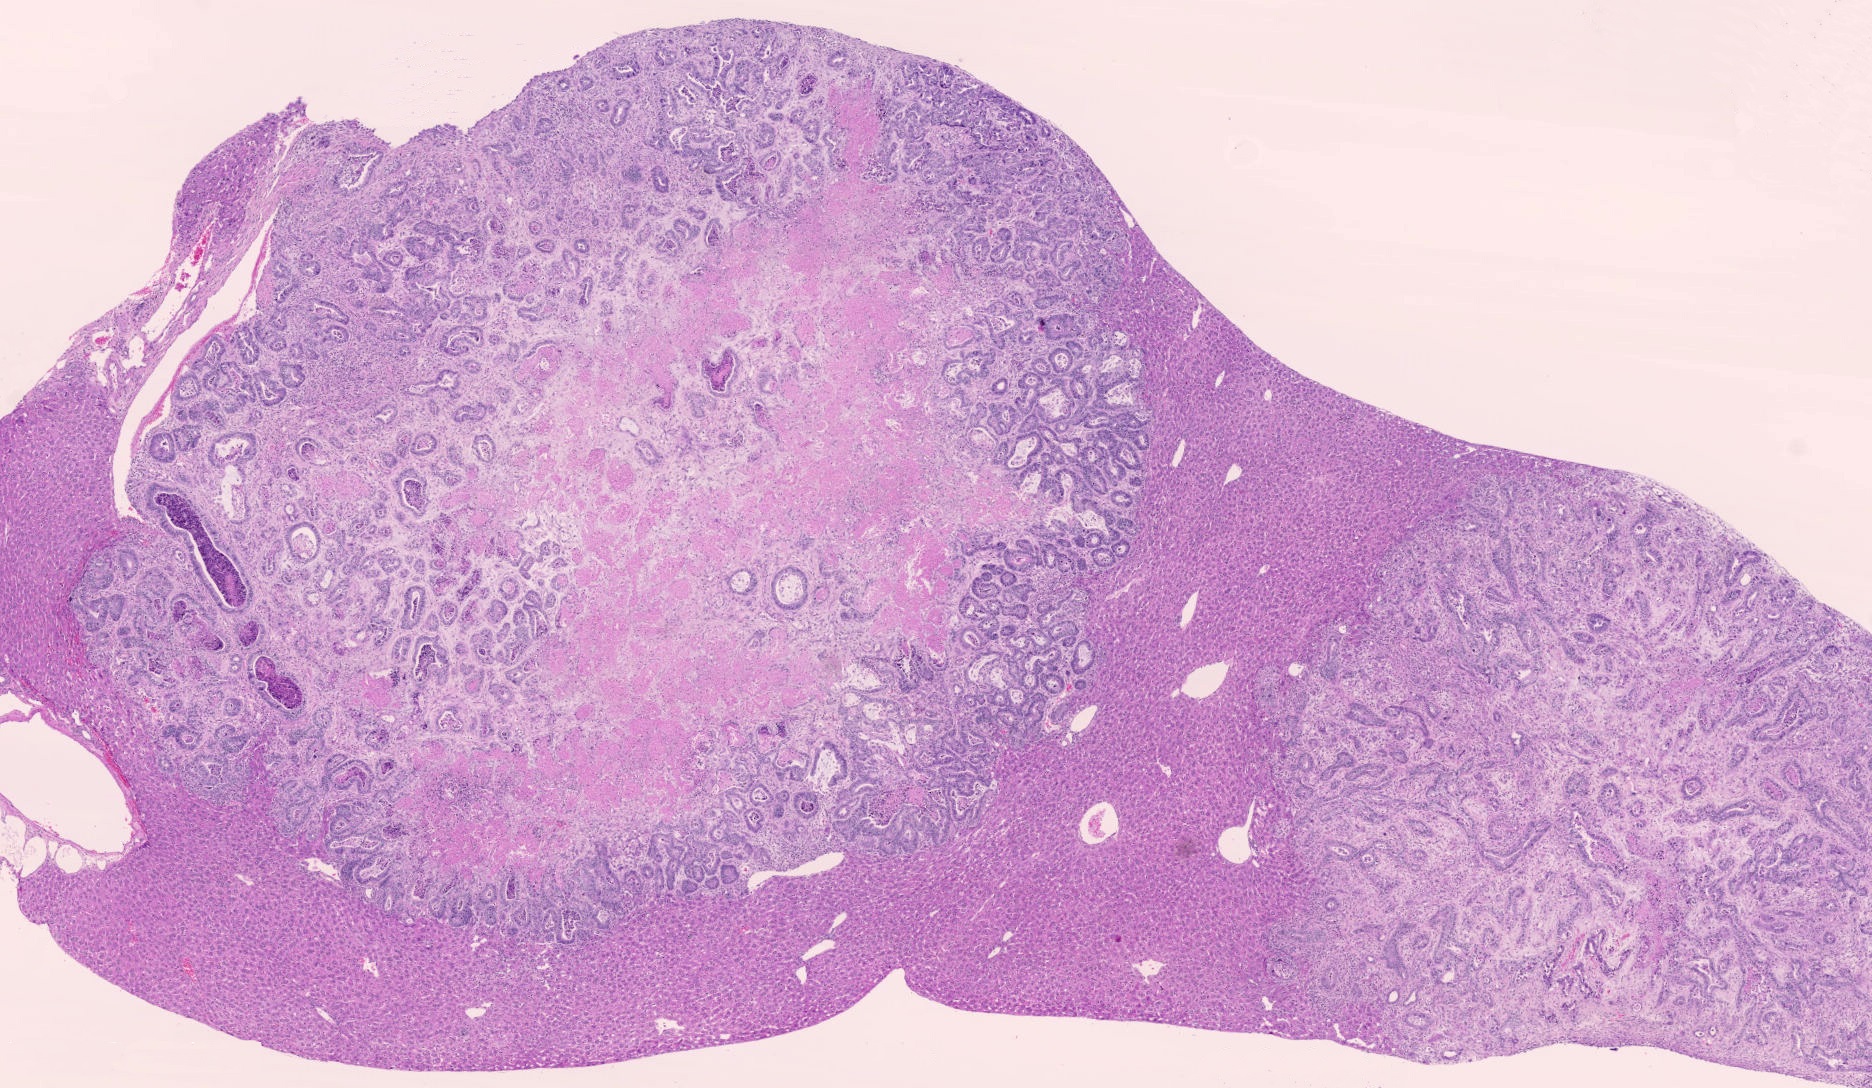

Oncopathology

LAMP offers specialised oncopathology expertise for research on experimental tumour models, with a strong focus on in situ tumour phenotyping, immunohistochemical marker evaluation, and assessment of invasion and metastasis. Our work supports both the development and validation of tumour models and their translational relevance to human cancer biology.